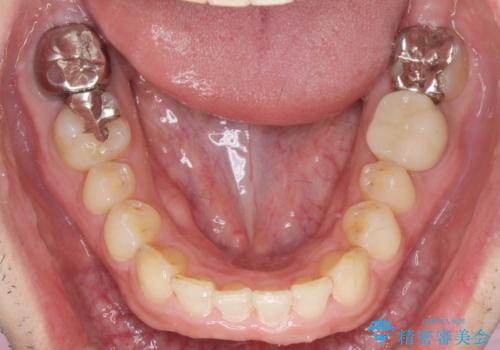

ディープバイトのマウスピース矯正

- 飛び出してしまい、隙間のある前歯をきれいに並べたい、と矯正治療を希望され来院されました。

上顎前歯を後方に引き、隙間を閉じるためには下顎前歯の絶対的な圧下を行い、深い噛み合わせを改善することが必要です。

圧下は歯の動きの中でも難しい動きの一つで時間がかかることが多いです。

前歯でチューイーをしっかり噛み、咬合圧を伝えたことで下顎前歯が圧下し、上顎前歯の隙間を閉じることができました。